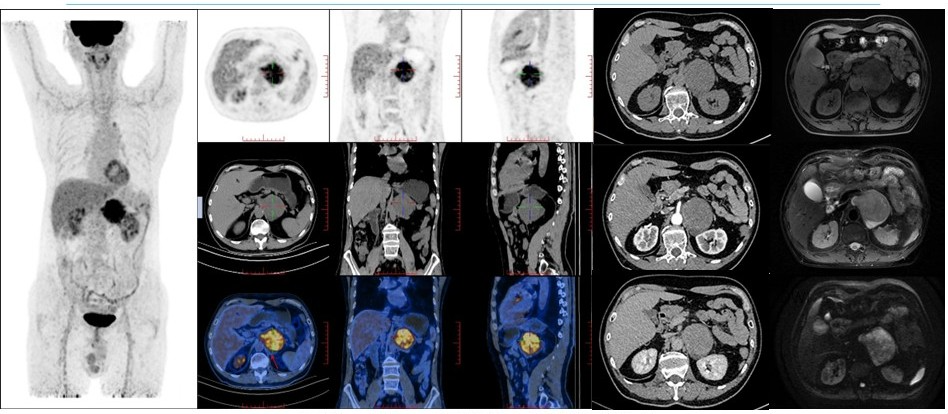

病例(12为一老年男性,体检发现左肾上腺肿物就诊,入院后监测血压轻度升高实验室检查示皮质醇水平轻度升高;增强CT检查示左侧腹膜后占位呈轻度强化,占位周围见片状低密度灶,MRIT1WIT2WIDWI高低混杂信号,周围见片状T1WI低信号、T2WI高信号灶;18F-FDG PET/CT示肿物代谢明显增高;(左肾上腺肿物)切除病理为神经纤维瘤。

12. 62岁,发现肾上腺肿物3月余神经纤维